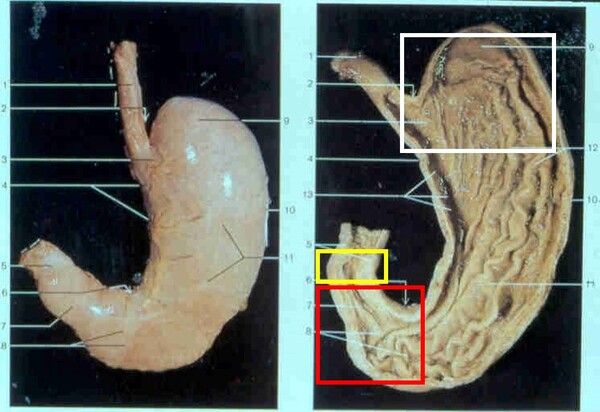

일부는 맞지만 오답이다. 위의 기능을 정리하면 세 가지다. 바로 '맷돌 기능', '창고 기능', 그리고 '보초 기능'이 그것이다. 입을 통해 식도를 거쳐 위에 들어온 음식물은 활발한 위 운동을 통해 잘게 부서지게 된다.

이러한 기능은 주로 근육층이 발달한 위의 하부에서 이뤄진다. 음식물이 위로 들어오면 위산을 포함하고 있는 위액이 분비되어 섞이게 되며, 외부의 유해한 성분이 소독되고 점차 암죽처럼 변하게 된다.

이러한 과정을 여러 번 반복하게 되는데 일단 한번 '맷돌 기능'이 작동된 뒤 일시적으로 위의 상부 쪽으로 옮겨져 보관된다. 이것이 '창고 기능'이다. 갈아서 부수는 기능과 일시 저장을 반복하다 보면 음식물은 미세한 크기로 잘게 쪼개지는데 이때 비로소 십이지장으로 보내지게 된다.

위와 십이지장 사이에는 강력한 밸브 역할을 하는 근육층이 형성돼 있어서 음식물이 완전히 처리되지 않은 채 십이지장으로 내려가거나, 반대로 십이지장에서 위로 역류하는 일을 예방한다. 이런 근육층을 유문이라고 하는데 이것이 '보초 기능'이다.

위 하부의 맷돌 작용과 위 상부의 창고 기능은 유기적으로 연결돼 가장 효율성 높은 작업을 하게 만들어져 있다. 이를 위해 위 하부는 단단한 근육층이 둘러싸고 내강이 좁은 반면, 위 상부는 위 벽이 얇고 크게 늘어나는 성질이 있어 충분한 양을 보관할 수 있게 한다.